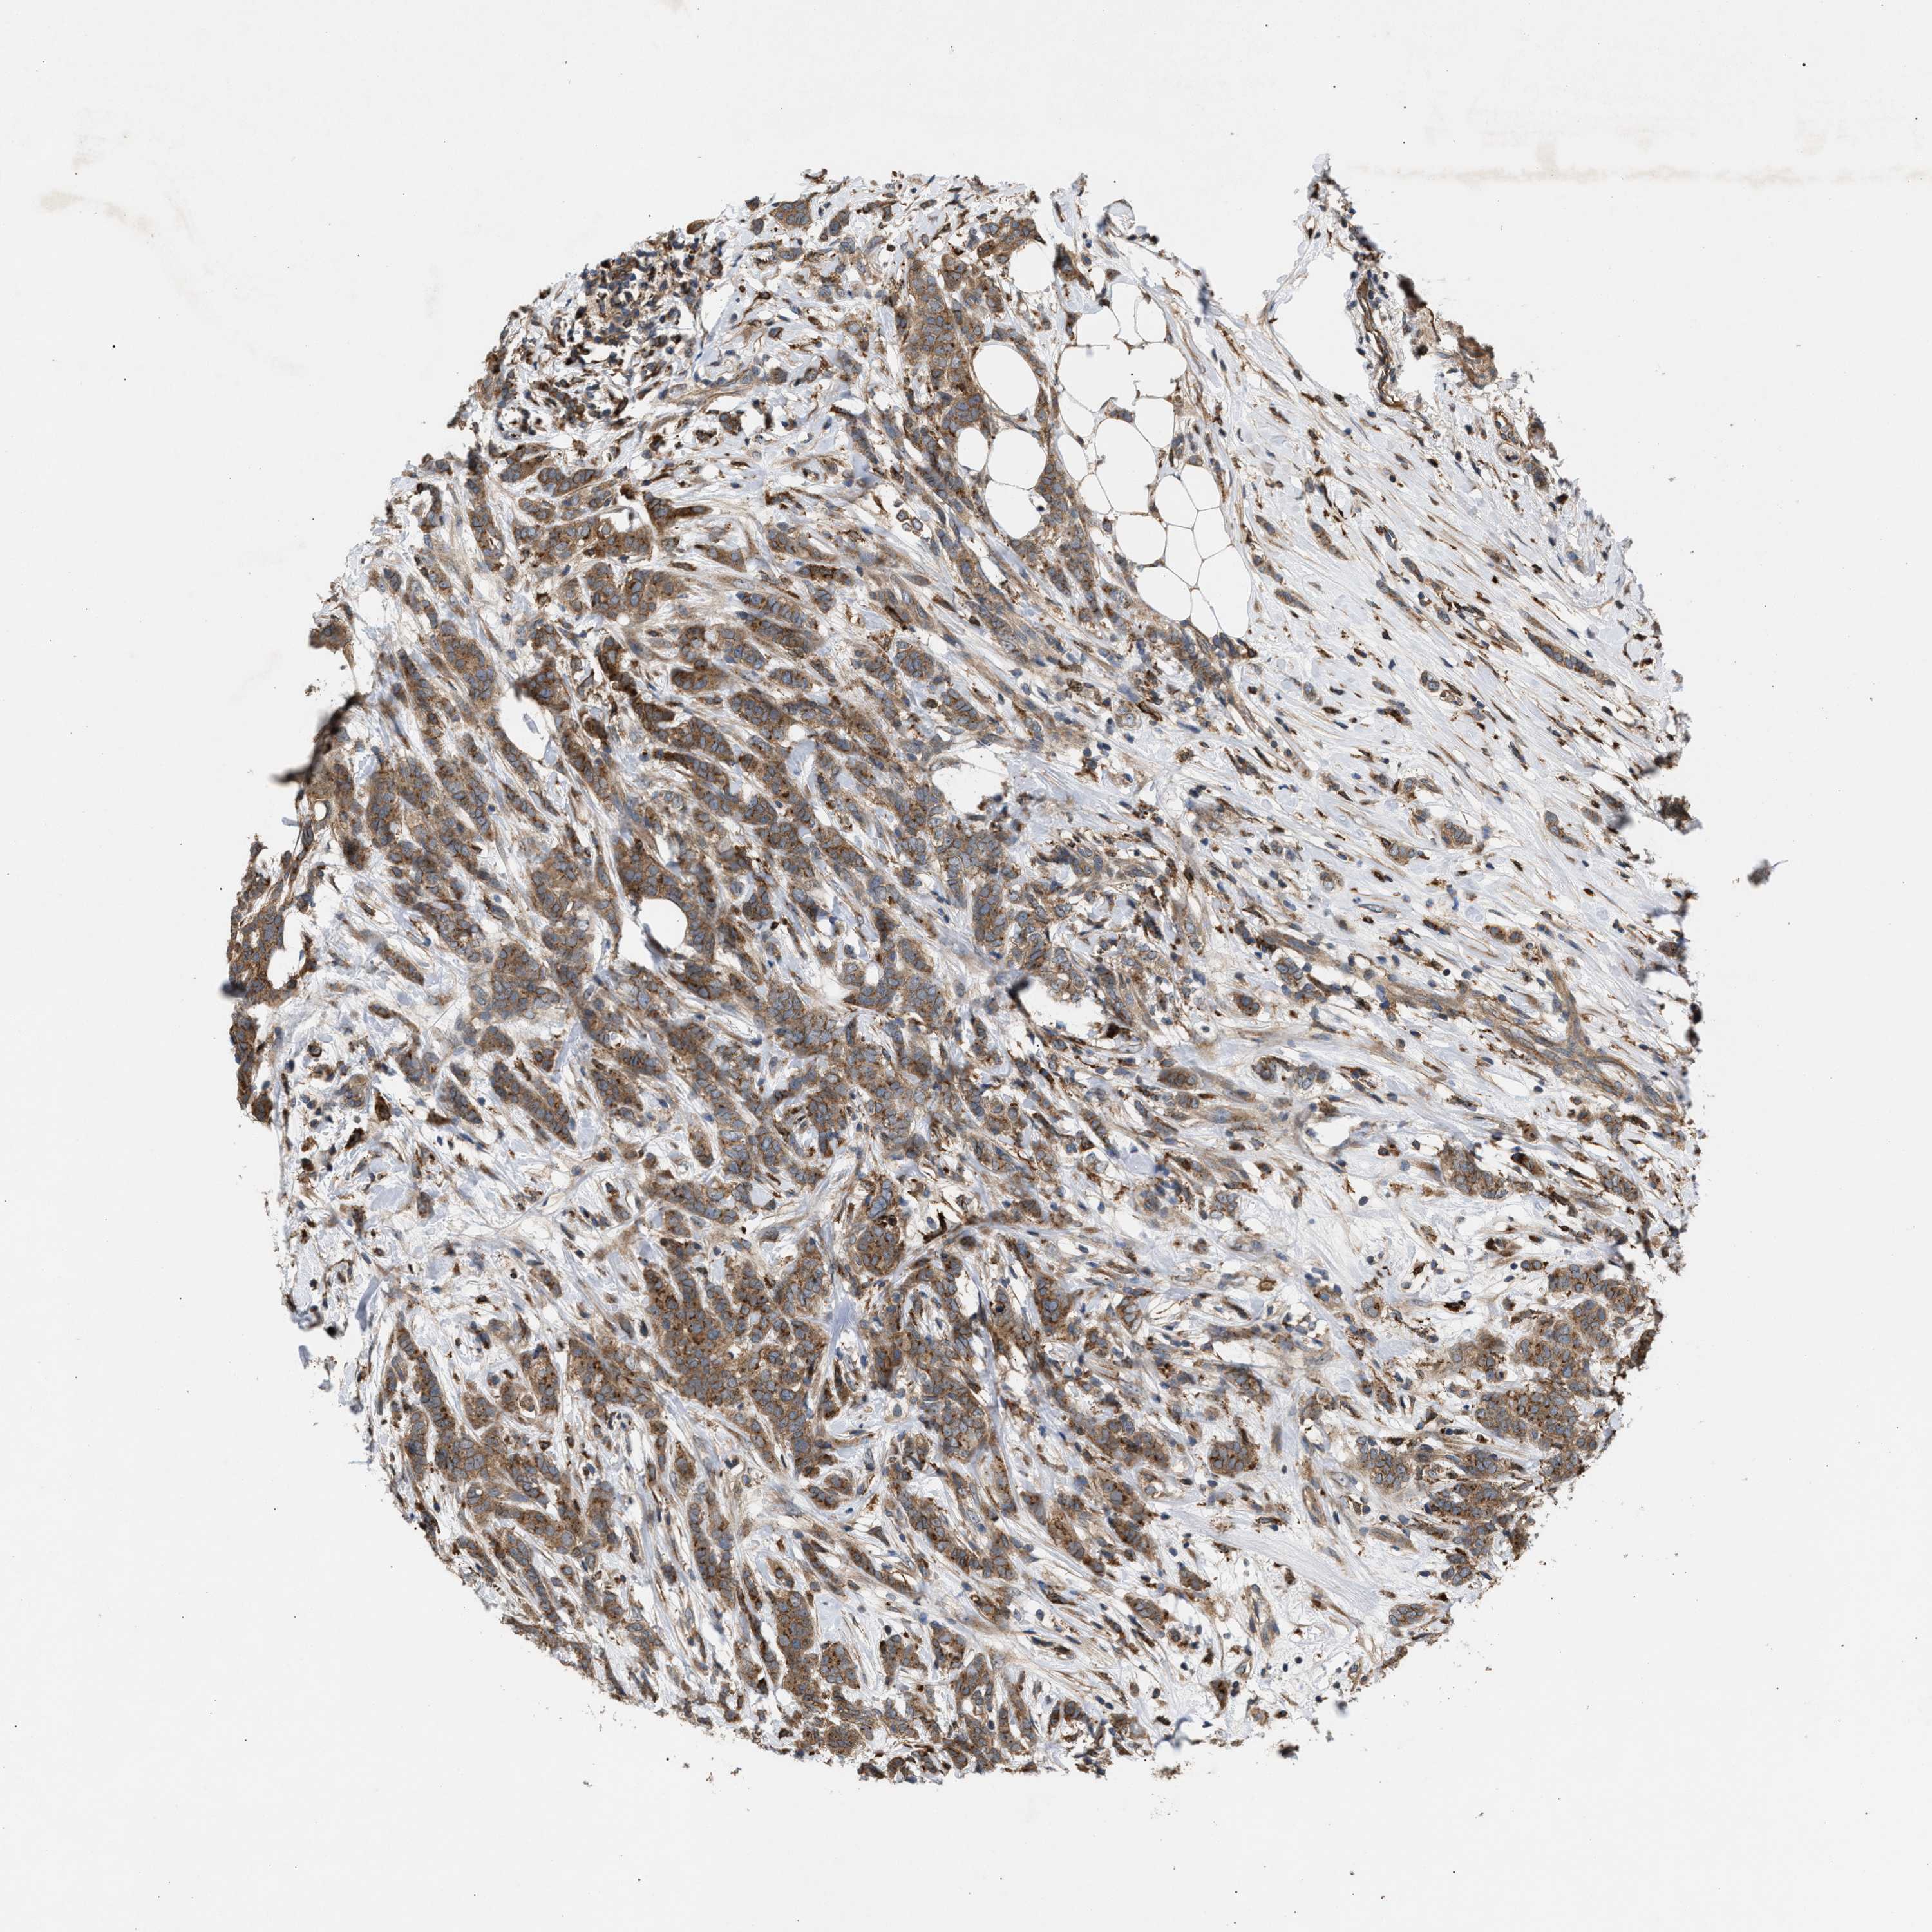

CANCER BREAST CANCER Show tissue menu

BRCA TCGA BRCA VALIDATION PROTEIN EXPRESSION